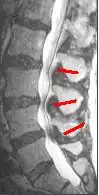

MRI

Since an MRI provides excellent imaging of blood vessels and tissues, it is recognized as the best type of imaging to observe signs associated with lumbar compression. The precise measurement of the diameter of the spinal canal is a particularly important component when determining the severity of the stenosis itself.[2] High strength 3-Tesla MRI machines are being utilized due to the increased vascular imaging capabilities. Better resolution capacity allows for more detailed observations by the healthcare provider. The sharp contrast of the high power MRI outlines details in the vertebra that are critical when examining a patient with lumbar spinal stenosis who may need a laminotomy.[1] MRI scanning post invasive surgery is used to see the quality of the surgery itself, yet the appropriate postoperative time elapsed before conducting an MRI is a debated topic.[2]

A CT scan is not the most effective imaging technique when observing lumbar abnormalities, however it can supplement an MRI by detecting certain degenerative processes. When determining whether or not a laminotomy will be beneficial for the patient, a healthcare provider must assess the severity of the possible abnormalities. Out of all the potential reasons to have a laminotomy performed, lumbar spinal stenosis is the chief reason. CT scans are used specifically to pinpoint a buckled lumbar ligamentum flavum as well as facet hypertrophy, which are some of the main pathophysiological changes indicative of lumbar spinal stenosis.[2] Even though a CT scan can reveal these pertinent signs of lumbar spinal stenosis, it can sometimes give a cloudy image due to the shadowing of the tissue contrast. When this occurs, an intrathecal myelography contrast is conducted with the CT scan to fix the abnormal contrast. A CT scan can also reveal an increase in the cross sectional area of the L3 vertebrae, which ultimately decreases the cross sectional area of the spinal canal.[2] As an increase in the size of the L3 vertebrae occurs, pressure builds up on the cauda equina, commonly causing pain in the lower back and lower extremities. Cauda equina compression can also be due to stenosis of L4-5 region as well.[1] Even though the CT scan allows for intensive image studying, the fixed nature of the image collection process alone is not enough to reach a definitive diagnosis of lumbar spinal stenosis. The outcome of the CT scan can help compile physiological evidence that the patient has lumbar spinal stenosis, and that the patient may potentially benefit from a laminotomy to improve his or her quality of life.[1]